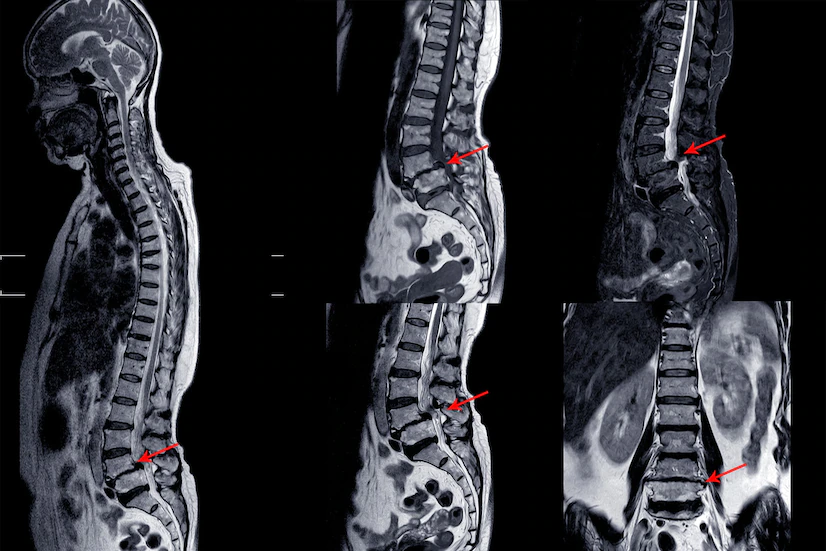

Spinal Infections/ Tumours

The spine is one of the most vital structures in the human body — providing support,….

Lumbar Canal Stenosis

Lumbar canal stenosis is a common spinal condition that occurs when the spinal canal..